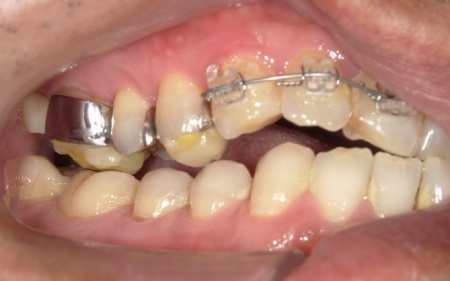

・前歯の噛み合わせ

下前歯が上前歯より前に出ている「反対咬合(こうごう)」で、将来的に歯や顎への負担が生じるリスクがあります。

・矯正治療

前歯の反対咬合については、部分矯正で改善を図ります。

前歯の噛み合わせ治療では、上顎の内側に歯を内側から動かす装置「リンガルアーチ」を装着します。併せて、上前歯の表面に「ブラケット」と呼ばれるボタン状の装置を接着し、そこにワイヤーを通して歯を動かす「マルチブラケット装置」を用いて部分矯正を行いました。